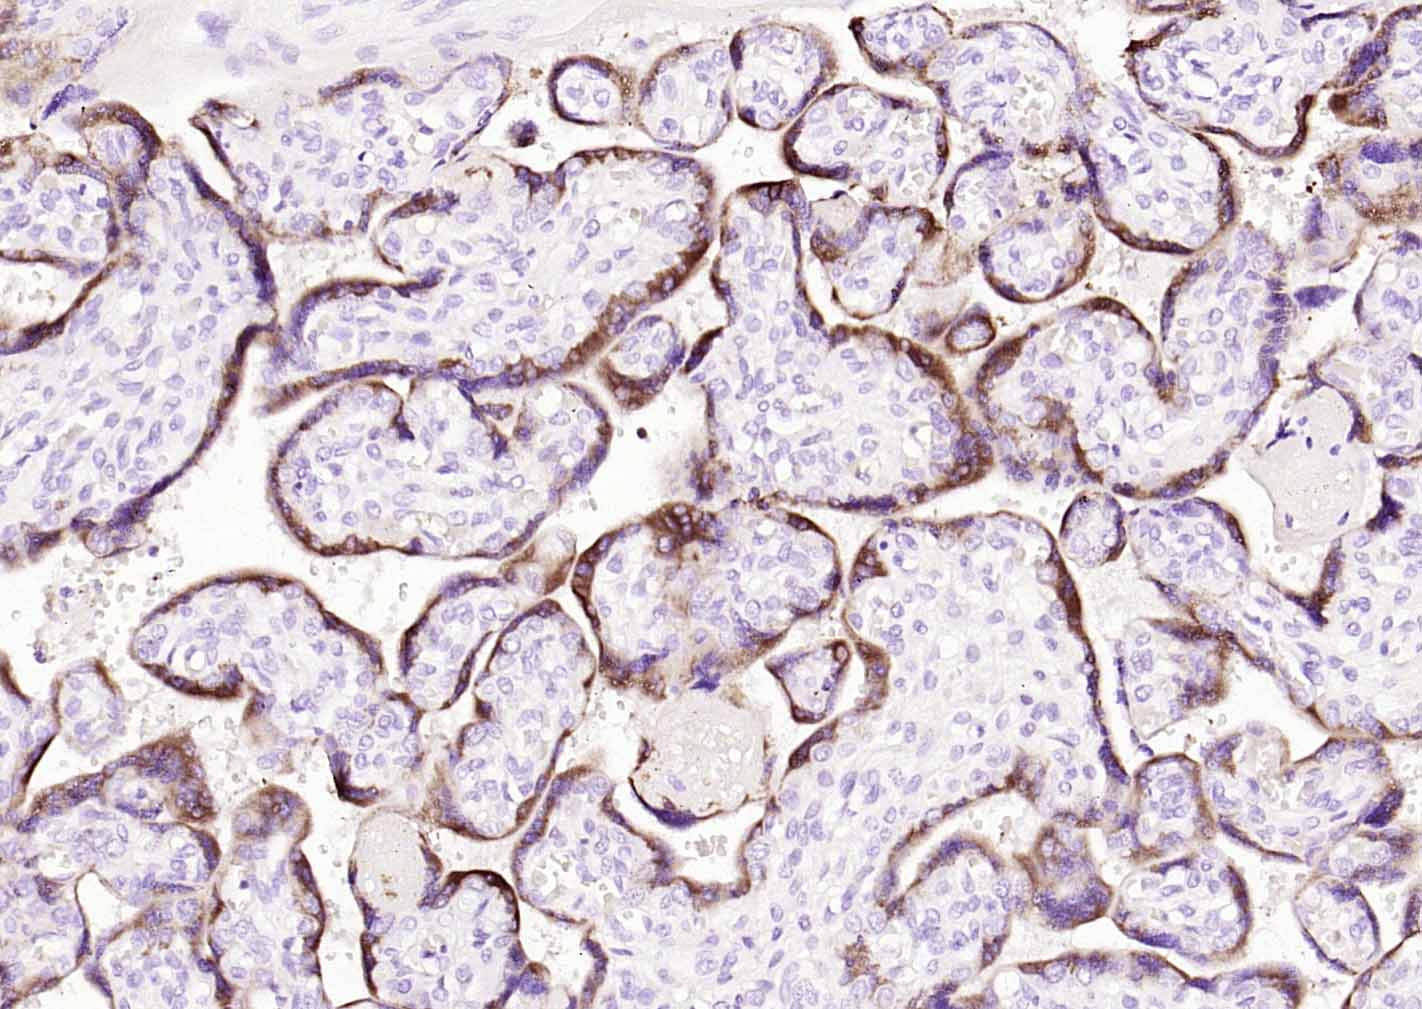

Paraformaldehyde-fixed, paraffin embedded (human placenta); Antigen retrieval by boiling in sodium citrate buffer (pH6.0) for 15min; Block endogenous peroxidase by 3% hydrogen peroxide for 20 minutes; Blocking buffer (normal goat serum) at 37°C for 30min; Incubation with (Placental Lactogen) Monoclonal Antibody, Unconjugated (bsm-60796R) at 1:500 overnight at 4°C, followed by operating according to SP Kit(Rabbit) (sp-0023) instructionsand DAB staining.